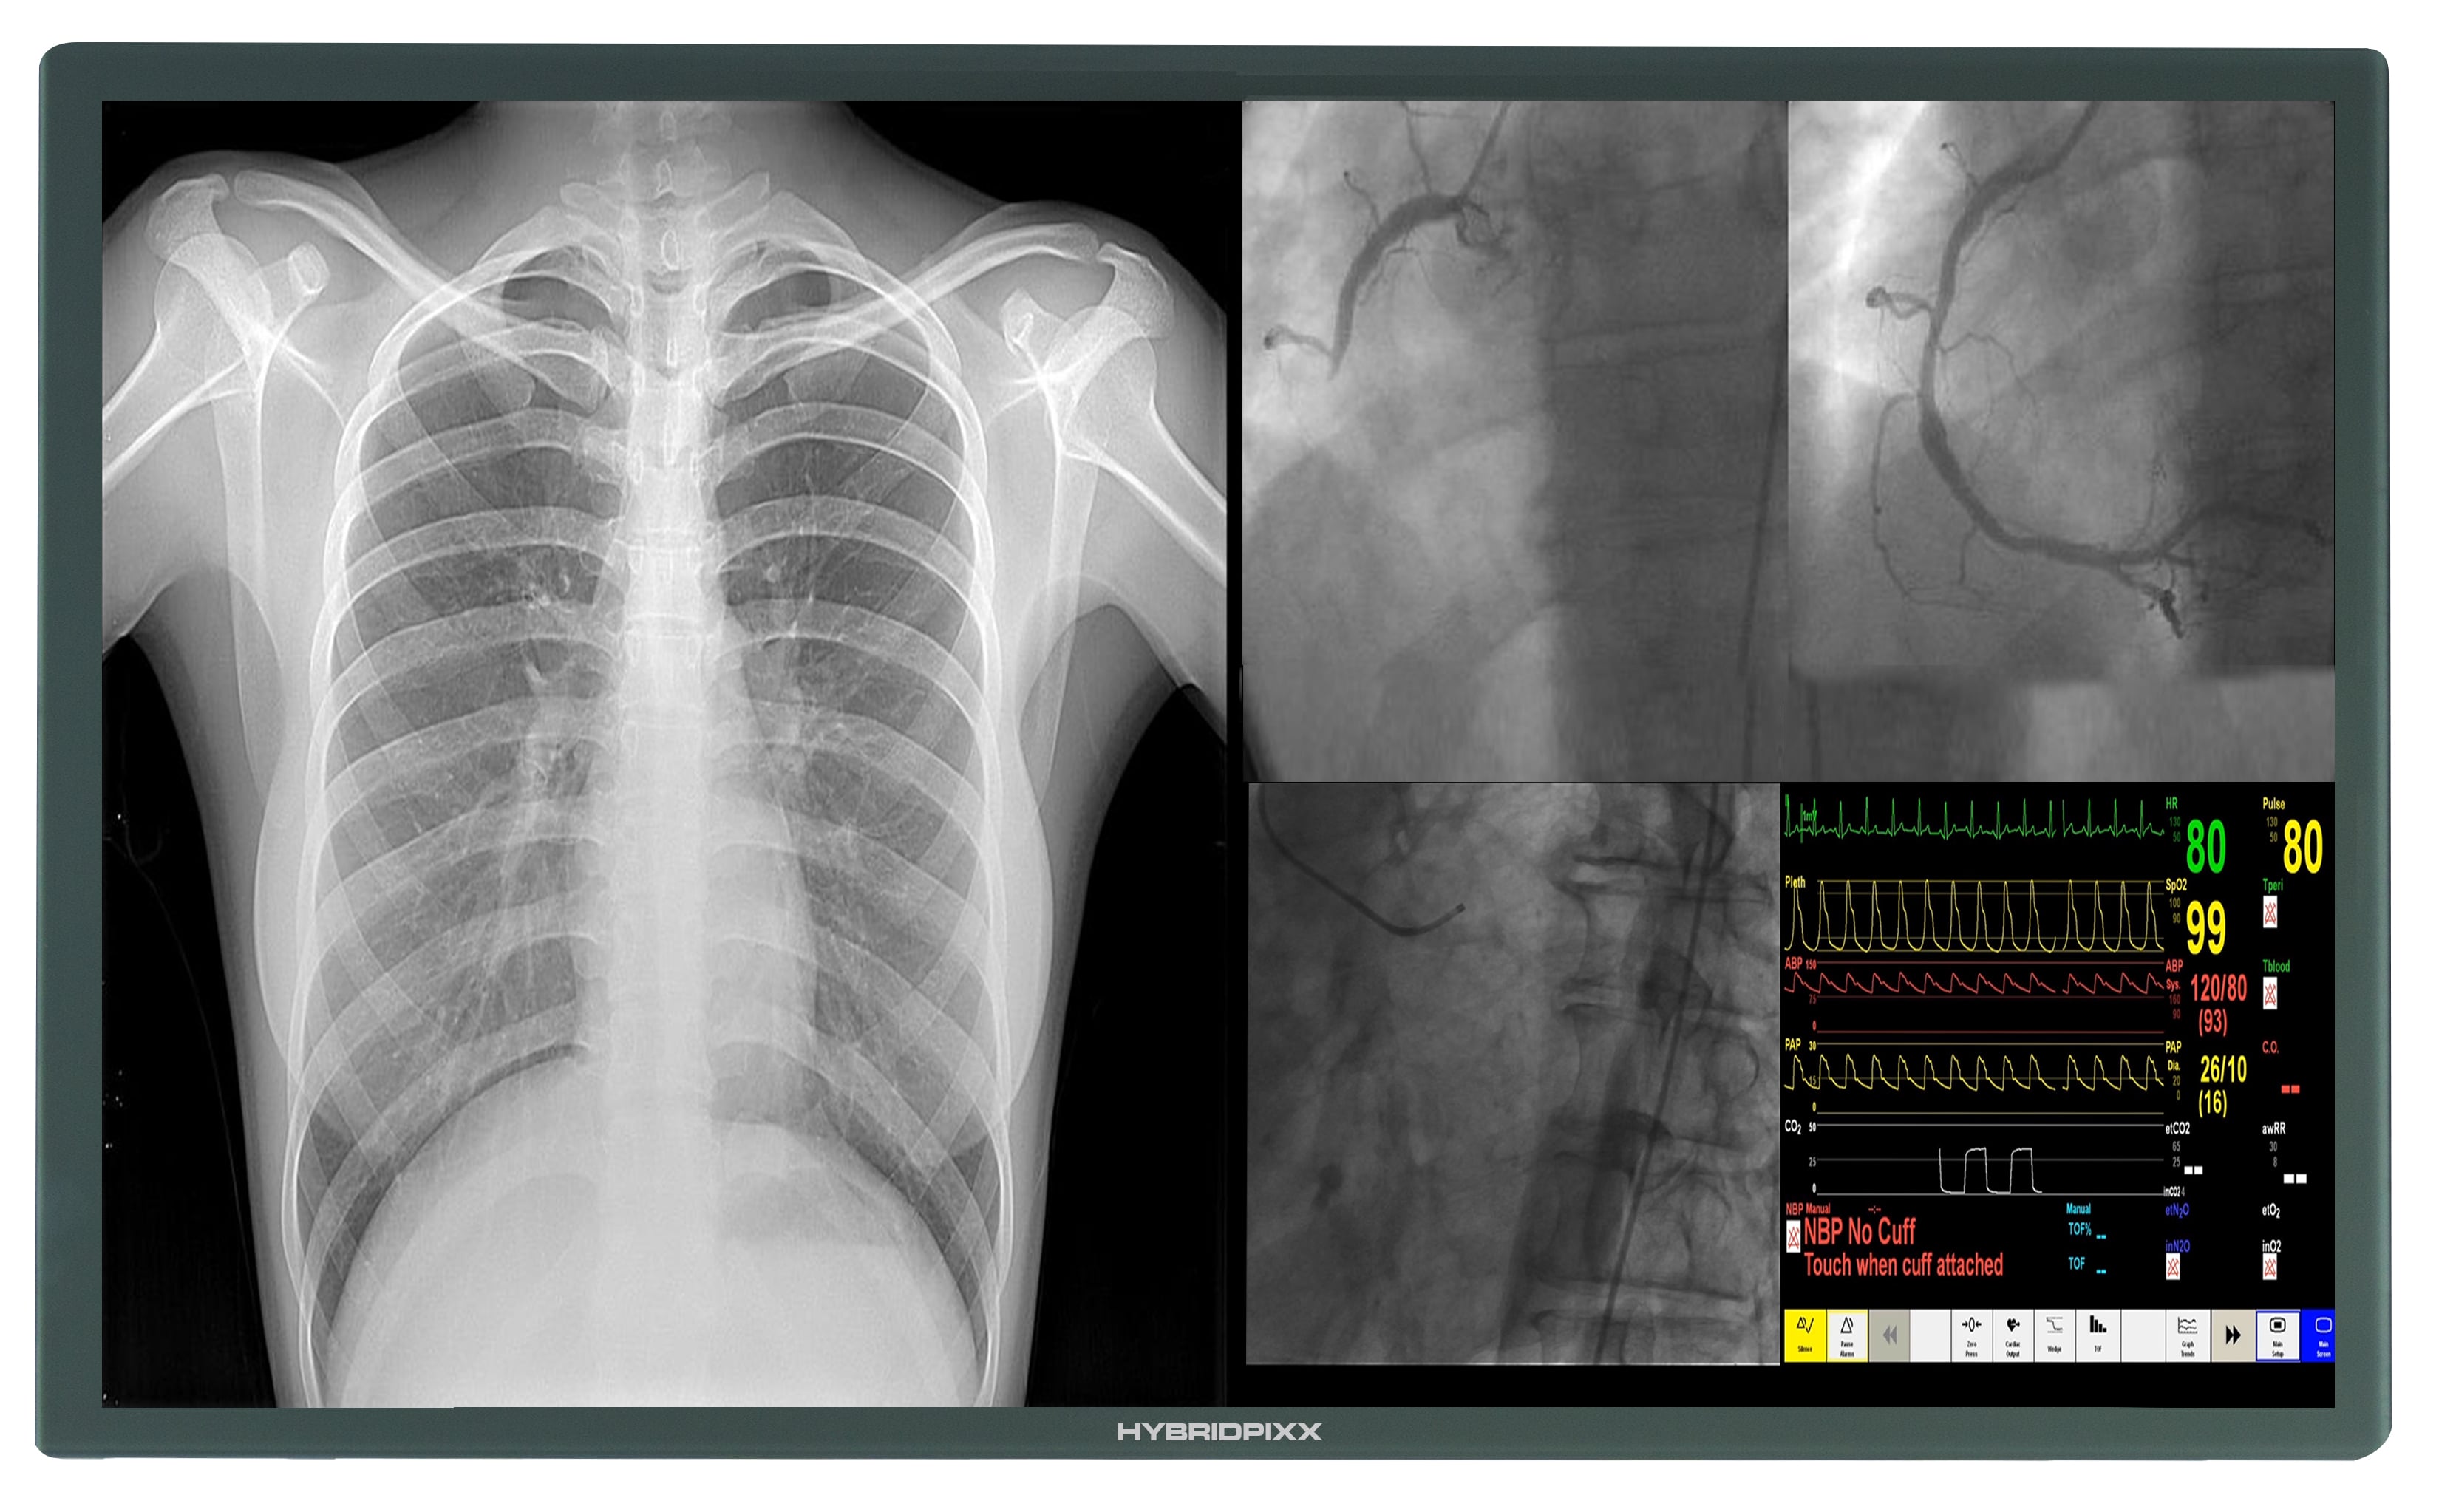

4K 8MP HD Cath Lab Display Monitor Screen

Instead of making use of four to six displays, many are instead opting to update their displays with one large UHD 4K display. When a UHD display is combined with a video manager, it has the ability to become customizable with a variety of layout options and editing tools like magnification. The design is easier to use and provides a higher resolution, making its adoption an easy choice as it facilitates precise procedures and minimally invasive surgeries.

The pending patent Hybridpixx touts an ingenious design that garners all the advantages of 4K UHD display, while mitigating the dangers associated with a single large display. The mount holds two 58 inch displays in place, so if the primary display fails, a back-up display with exactly the same parameters is ready. With a modular connection, the wireless display can be easily switched in under a minute.

Available in 58 inches, the 4K UHD monitor can be employed in both analog and digital cath labs. With the option to purchase our video manager, all the benefits of customizable layouts and modification are possible as well. Additionally, it can be utilized in a variety of spaces, including hybrid operating rooms that facilitate both surgical and interventional procedures.